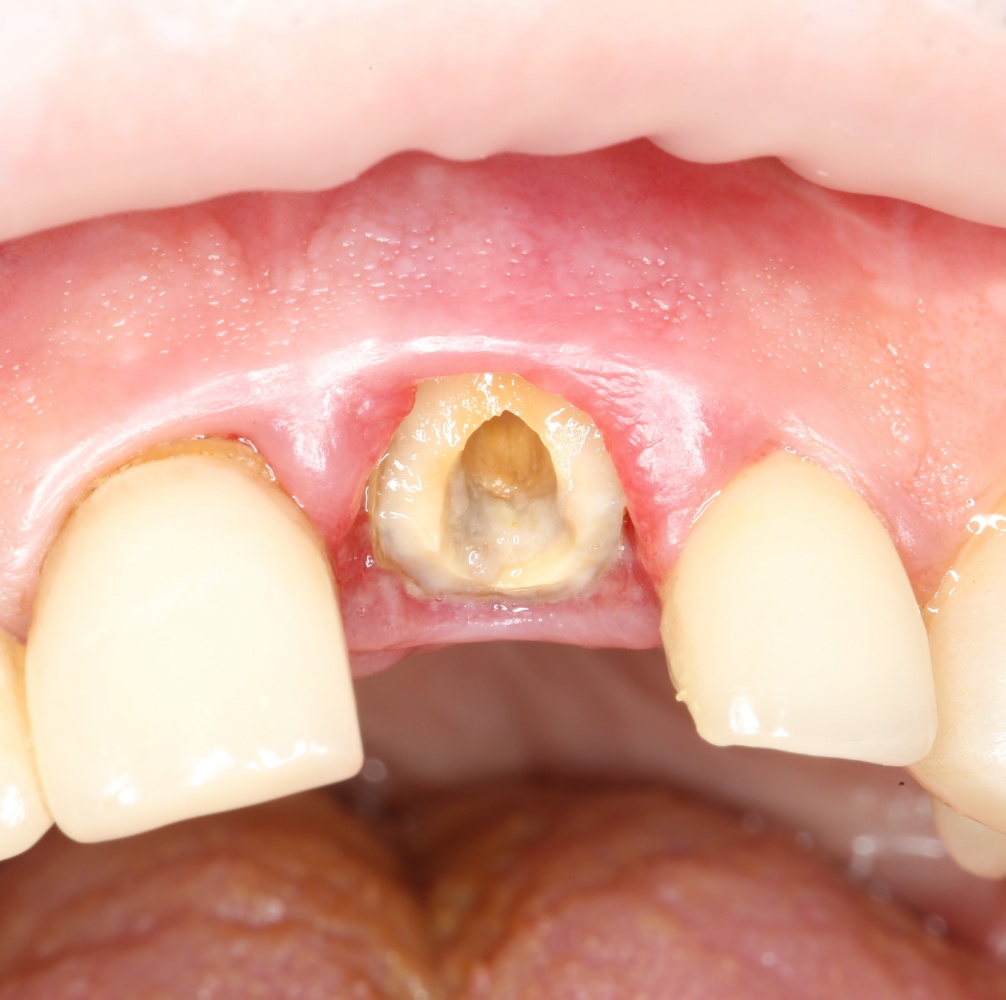

Рекомендации по установке имплантов. Для всех. Часть V.